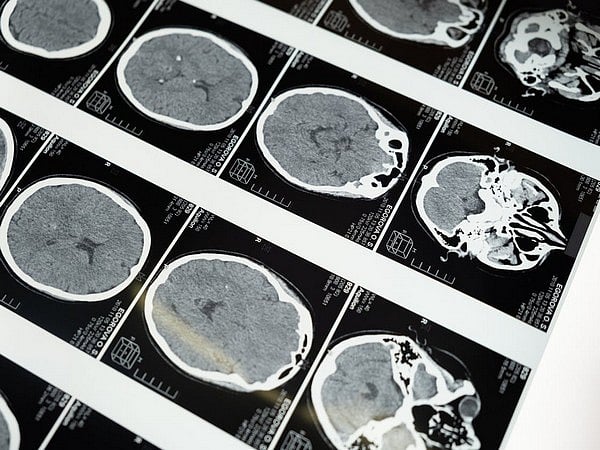

Researchers from the University of Colorado (CU) Cancer Center has found that the youngest patients with brain tumours - those ages from 0 to 3 months - have about half the five-year survival rate as children ages 1 to 19. The study was published in the journal, 'Journal of Neuro-Oncology'. Adam Green, MD, an associate professor of pediatric haematology/oncology in the CU School of Medicine, and his co-researchers analyzed population-based data for almost 14,500 children ages 0 to 19 who were diagnosed with brain tumours.

Green and his co-researchers used data from the National Cancer Institute's Surveillance, Epidemiology, and End Results (SEER) Program, a national cancer registry that covers more than a quarter of the U.S. population and represents the extensive diversity of the country. The researchers extracted SEER data relating to childhood brain tumours and divided it into three age groups - 0 to 3 months, 3 to 6 months, and 6 to 12 months. They compared data in these three groups with brain tumour data in people ages 1 to 19. What they discovered, Green said that "the types of brain tumours that babies get are different than in older patients, and that's an important finding in and of itself. The most important findings we had were that the survival that babies have from brain tumours is worse than older kids for almost all of the types of brain tumours we study."

Further data analysis showed that five-year survival in the 0 to 3 months age group is between 30 and 35 per cent, whereas five-year survival in the 1 to 19 age group is about 70 per cent. Five-year survival in the 3 to 6 month and 6 to 12 month age groups was also significantly lower than in older children.